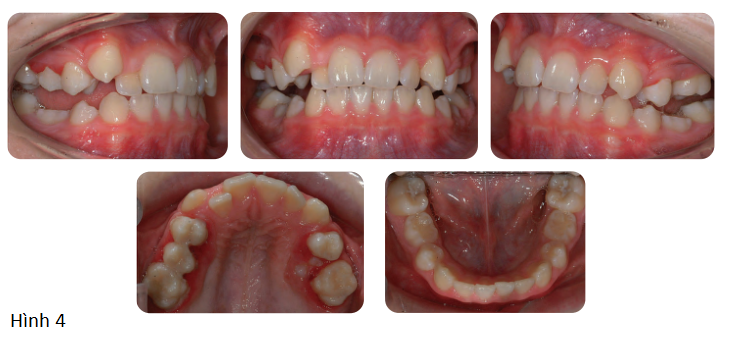

Bệnh nhân nam 10 tuổi tới phòng khám nha khoa vì không thích vị trí của răng nanh hàm trên và khớp cắn. Không có tiền sử y khoa liên quan. Bệnh nhân có sai lệch khớp cắn hạng III với kiểu xương hạng III trung bình, chiều cao tầng mặt dưới trung bình, mức độ chen chúc nặng, R25 mọc ngầm và cắn chéo răng cửa mà không có trượt chức năng trên cung răng hỗn hợp giai đoạn cuối. (Hình 1)

Phần lớn các trường hợp sai khớp cắn hạng III được thấy ở tuổi vị thành niên và thanh thiếu niên, những người có phần xương bên dưới biểu hiện thiểu sản xương hàm trên ít nhiều. Một cách lý tưởng, điều trị những trường hợp này nên đặt mục tiêu là làm chuyển hướng và kích thích tăng trưởng xương hàm trên theo chiều trước sau. Một cách để đạt được điều này là sử dụng lực ngoài mặt dưới dạng của headgear kéo ra trước. Nó được thiết kế để tạo hiệu ứng “chỉnh hiafnh” đạt được thay đổi xương cùng với di chuyển răng-xương ở răng. Facemask được đeo gần như 24 giờ/ngày nếu có thể, cho đến khi đạt được độ cắn chìa dương. Trong trường hợp này, độ cắn chìa được chỉnh sửa trong 9 tháng, và đạt được +4mm.